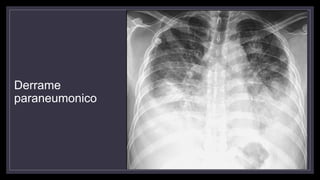

Derrame paraneumonico

• Se debe a aumento de la permeabilidad en la pleura visceral debido al proceso

inflamatorio adyacente.

• Son exudados estériles con nivel de glucosa entre 40 – 60 mg/dl y pH mayor a 7.20

• Son pequeños

• No suelen ser localizados

• Imagen en menisco

• Se resuelven con tto antibiótico

Derrame

paraneumonico